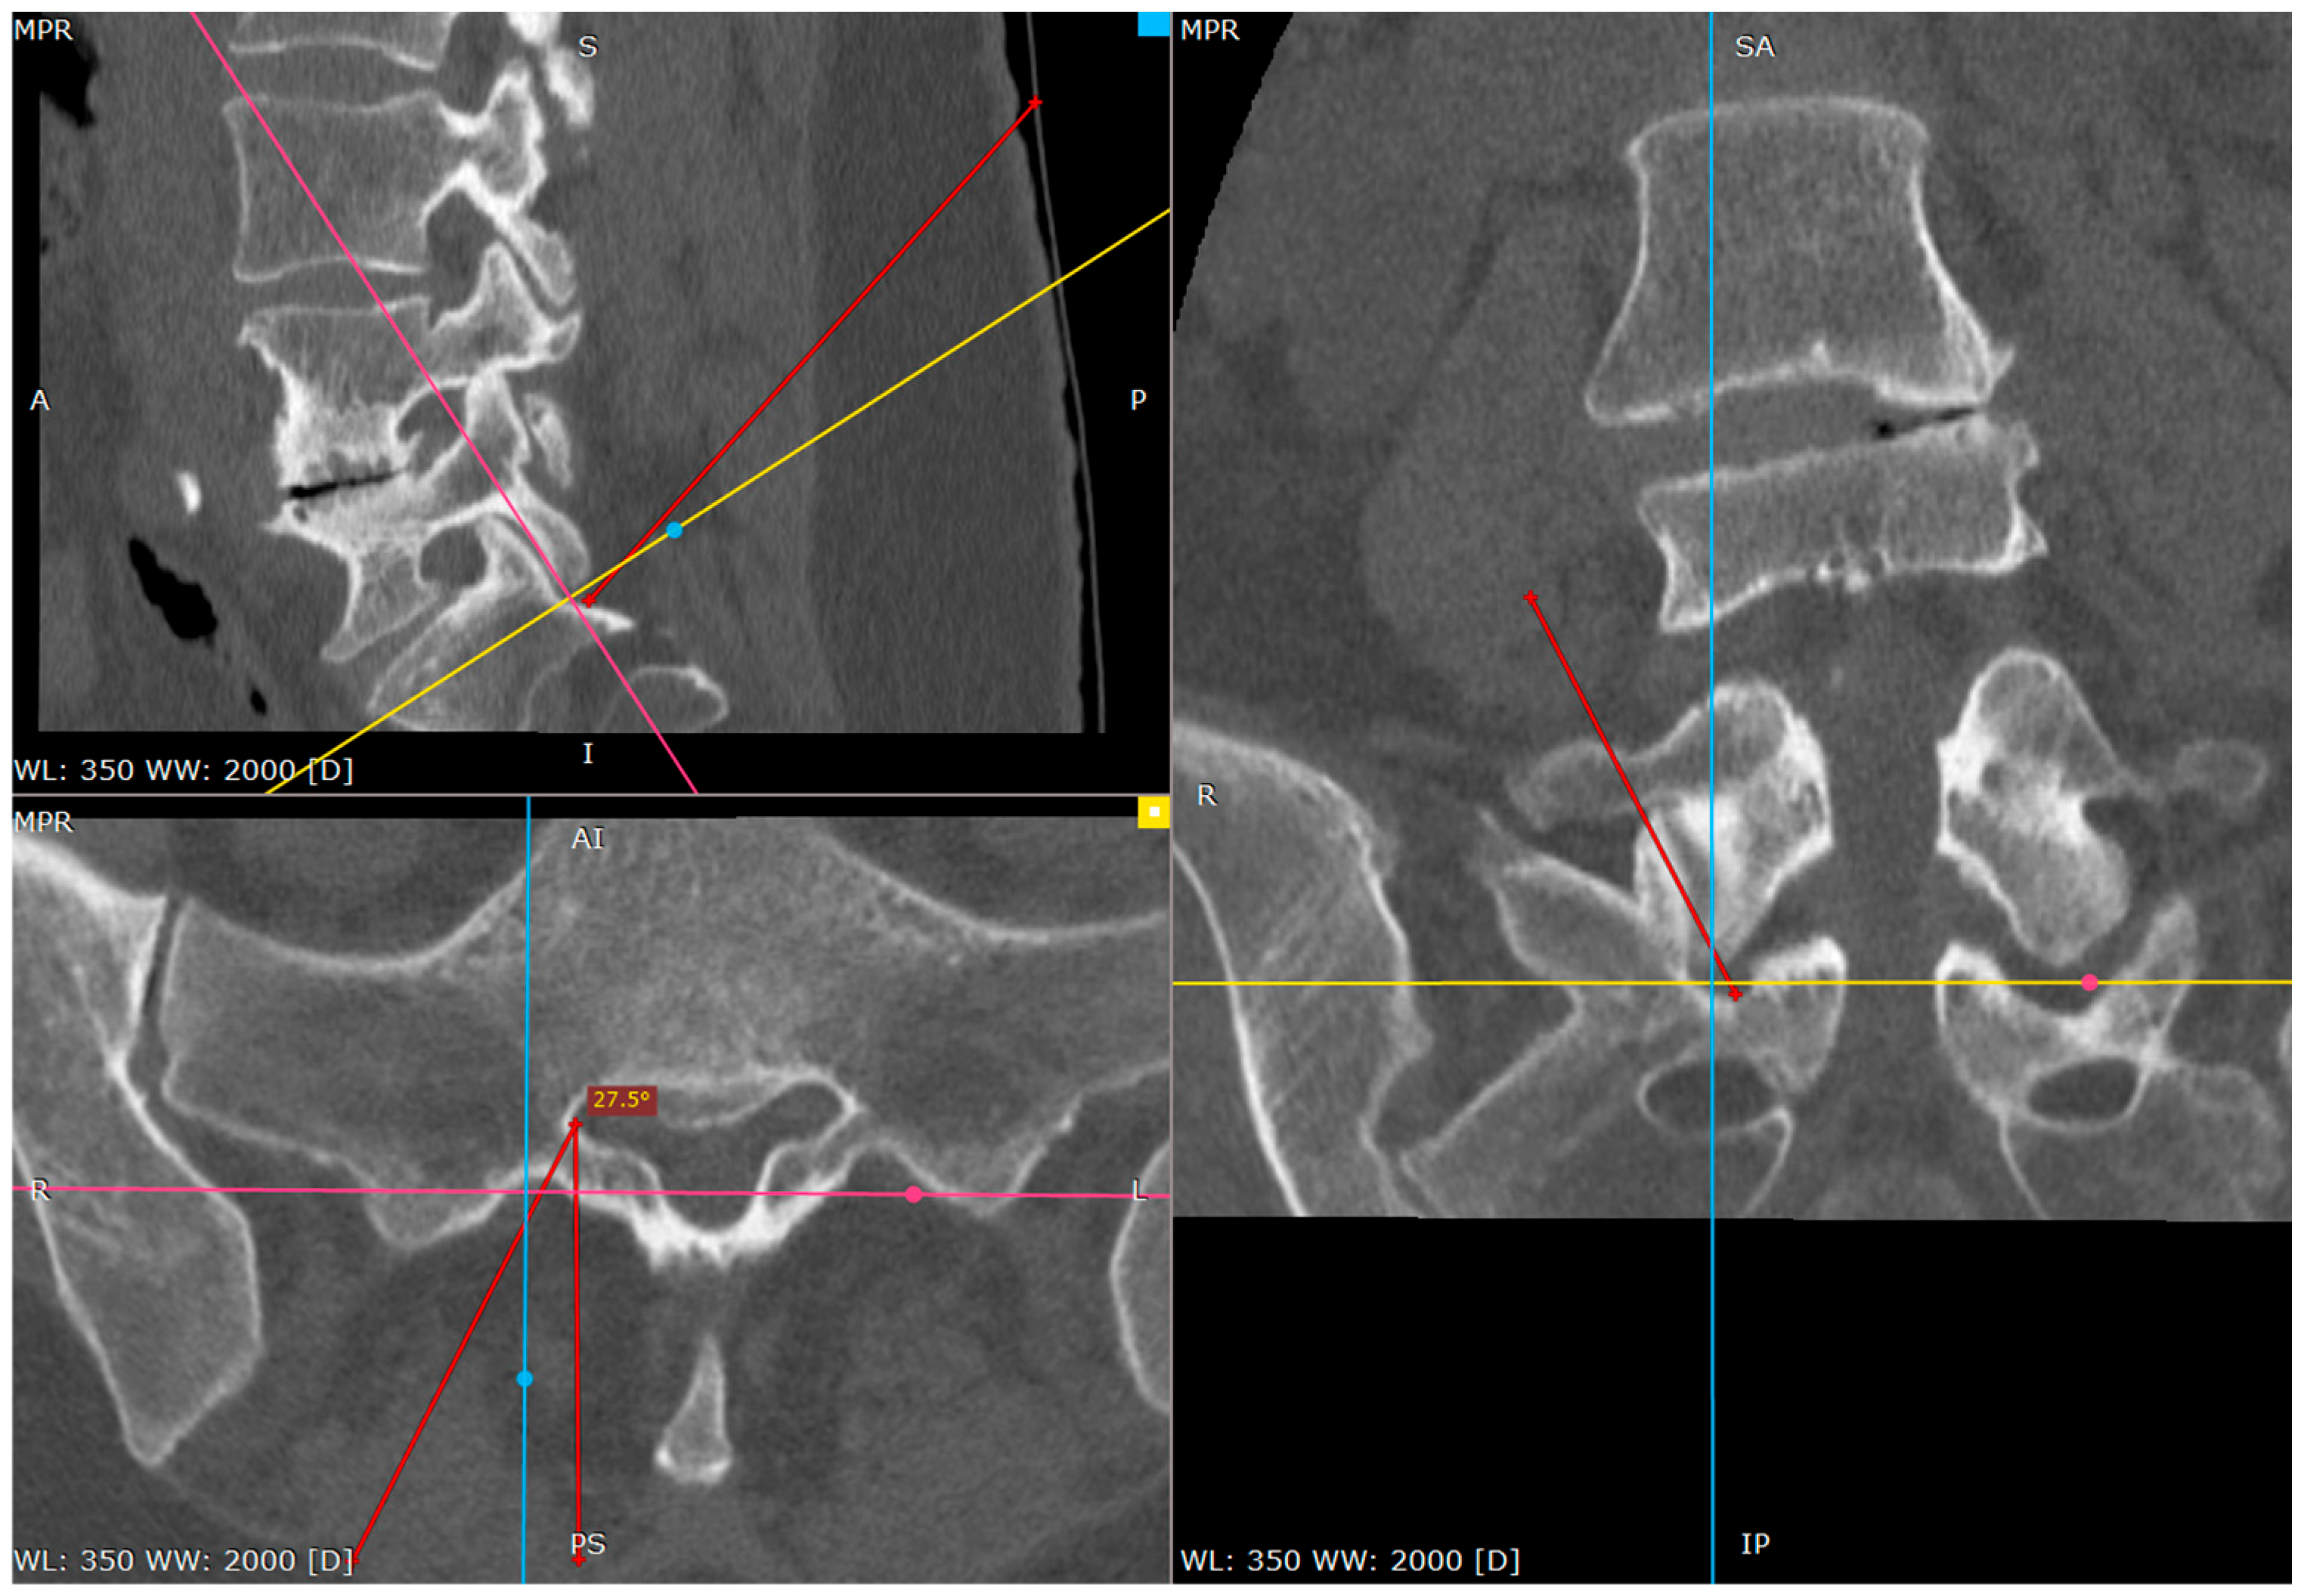

As the needle is placed against the S1 facet it is the secure spot (Figure 4 and Figure 5).

The S1 facet has a cradle-like shape in the transverse plane, so there is no risk of spinal canal violation, as long as it is lateral to the medial border of the S1 inferior facet in the AP view, which is being used from the beginning of the procedure.

The operator can check it by tapping with the tip of the needle toward the midline. There is a sensation of the upward slope; the sudden advancement of the needle with no bone contact necessitates the verification of the needle tip.

Figure 4. Needle against inferior part of S1 facet surface (CT tri-plane reconstruction).

Figure 8. Approach angle and needle trajectory to facet with intent to approach S1 root (CT tri-plane reconstruction).

Figure 9. Approach angle and needle trajectory to S1 root (CT tri-plane reconstruction).